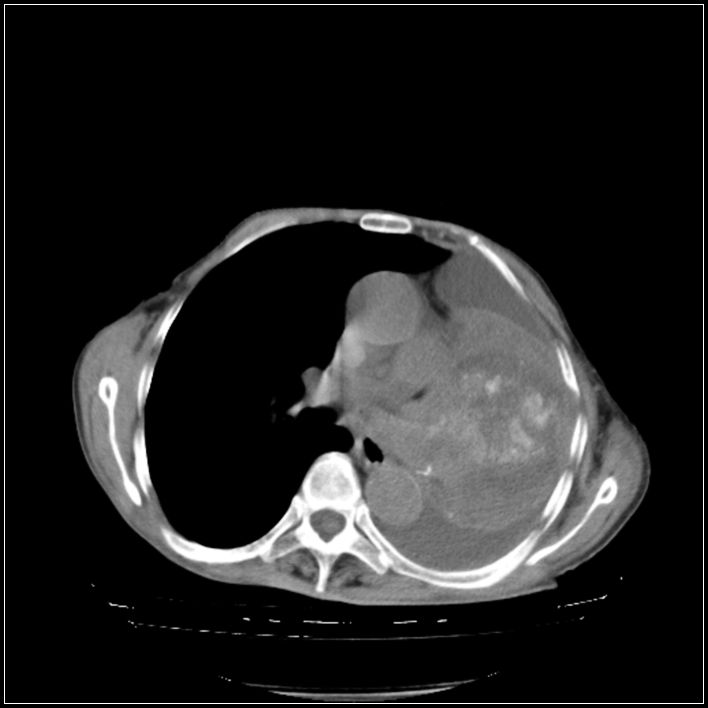

以下是引用影象小辈在2008-5-31 16:25:00的发言:[br]左侧胸腔团状不规则致密影,界欠规整,密度不均匀,其内可见更低密度影及高密度影,并可见包裹性胸腔积液 考虑为1.畸胎瘤 2.肺癌